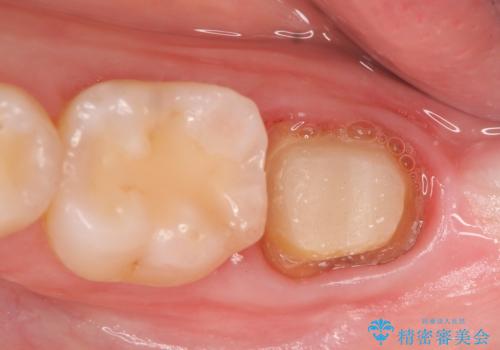

診査の結果根尖病変を認めたため再根管治療を行った後に、被せ物を入れるスペースを作るため歯冠延長術を行いました。

歯冠長延長術とは歯肉弁根尖側移動術とも言い、歯の高さが低くクラウン(被せ物)による治療が難しい場合に、歯茎を歯根方向に下げることで歯の高さを確保する手術です。歯の高さが十分にあることで、外れにくいしっかりとしたクラウンを被せることができます。